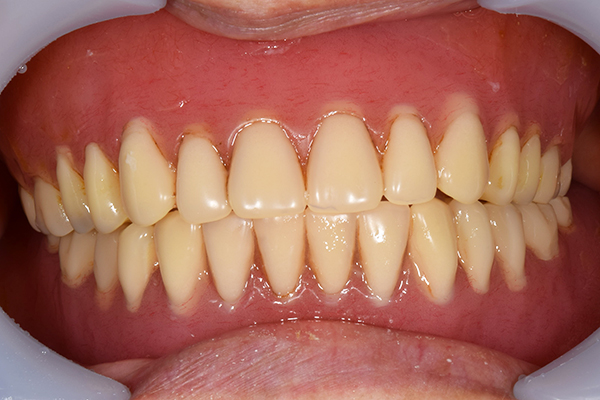

ケース2(自費の総入れ歯と部分入れ歯)

上下の入れ歯が外れやすくなったということでいらっしゃいました。 顎の骨はしっかりしていましたので、精密な型取りさえすればしっかりした入れ歯がつくれると思いました。 また下には6本歯が残っていましたが、虫歯になっている歯もありました。 かぶせ物のなかで大きな虫歯があった歯があり、1本だけ残せない状態でした。

上の入れ歯は確かに吸着は甘くなっていました。 また下の入れ歯はバネの一部が壊れており、安定感がなくなっていました。

精密な型取りの後、噛み合わせのチェックをしていきました。 かぶせ物も同時に作っていきました。

歯を並べた後、かぶせ物のフレーム作ってもらいました。先に歯を並べて理想の位置を決めておくことが大切です。

完成した入れ歯とかぶせ物です。 入れ歯への寛容度が高い患者様でしたので、 金属は使用せず、プラスチックのみで上は仕上げました。 下顎も歯は1本減ってしまいましたが、しっかり 入れ歯が維持できる様な構造にしました。

お口の中に入れた状態です。 見た目も最初とほとんど変わることなく作成できました。 維持や吸着に関しても問題ないようでした。

年齢 80歳・女性

主訴 上下の入れ歯が外れやすくなった

治療期間 3ヶ月

治療費 .メタルボンドクラウン:550,000円

.義歯:990,000円(税込、上下)

治療方針 長年使ってきた義歯の人工歯が磨耗し、臼歯部での咬合がすくなくなり、入れ歯の安定も悪くなり、あたりどころが悪くなって痛みが出ている。 そのため、入れ歯を上下作りかえる必要がある。

治療内容 過去に治療を行ったことのある歯が再度虫歯になってしまっているところがあり、すでに残せない状態にまでなっていたため、歯を一本抜歯した。 その後、かぶせ物と入れ歯を同時に作成していった。

特記事項 歯を抜いた後は、2〜3ヶ月歯ぐきの回復を待ってから入れ歯を作るため、待機期間があります。その間、古い入れ歯を調整しながらそのまま使うか、新し物をつくっておく必要があります。ただし、入れ歯は保険治療で作成する場合、6ヶ月は新しいものが作れないという決まりがあるので保険で全て作りたい場合は注意が必要です。